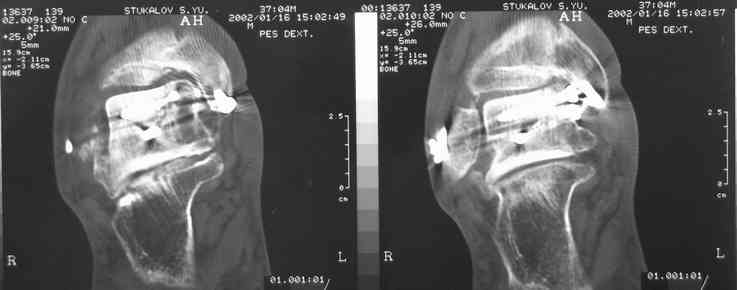

Случай с множественным оскольчатым переломом тарана оперированный из двойного доступа.

Через 2 мес.:

Через 8 мес.:

Через 14 мес.:

Для оценки состояния нужны дополнительные исследования, например

> Canale или Broden ренгенограммы

повторили рентгенограммы и доделали проекции, к единому мнению все еще не пришли

На ренгенограмме не уловил многоскольчатость тарана, чтобы доказать, конечно, можно было исследовать на КТ, потом КТ дает ориентацию фрагментов.

Два фрагмента суставной поверхности тарана можно восстановить боковой компрессией шурупами и дополнительно костная пластика.

(кстати, на нашем случае была применена костная пластика-allograft crouton для заполнения дефектов)

Наружный фиксатор "голень-пятка", "лигаментотаксис" при поступлении, домой через 48 часов после обучения ходьбы на костылях, в течение ближайшего времени осмотр в поликлинике для определения кондиции мягких ткани (тест на образование морщин в зоне разреза), при отсутствии отека примерно на 6-7 день с момента травмы операция.